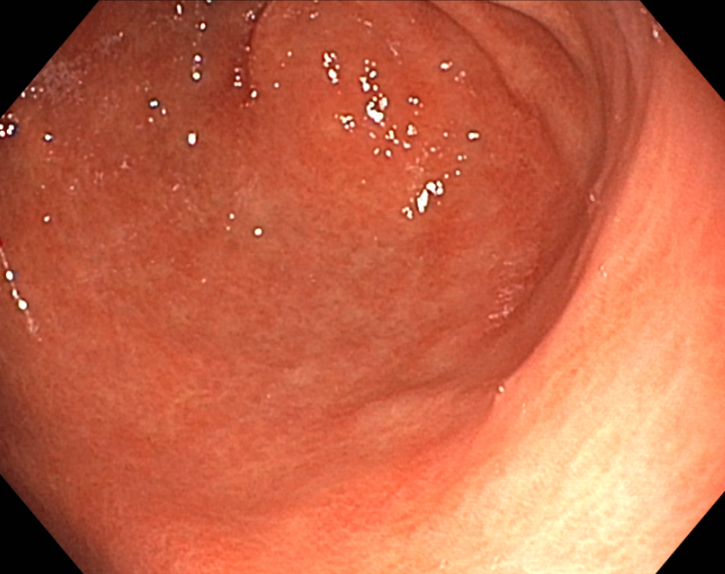

다음은 위내시경에서 확인된 위분문부와 유문부 점막에 생긴 급성위점막병변 사진입니다.